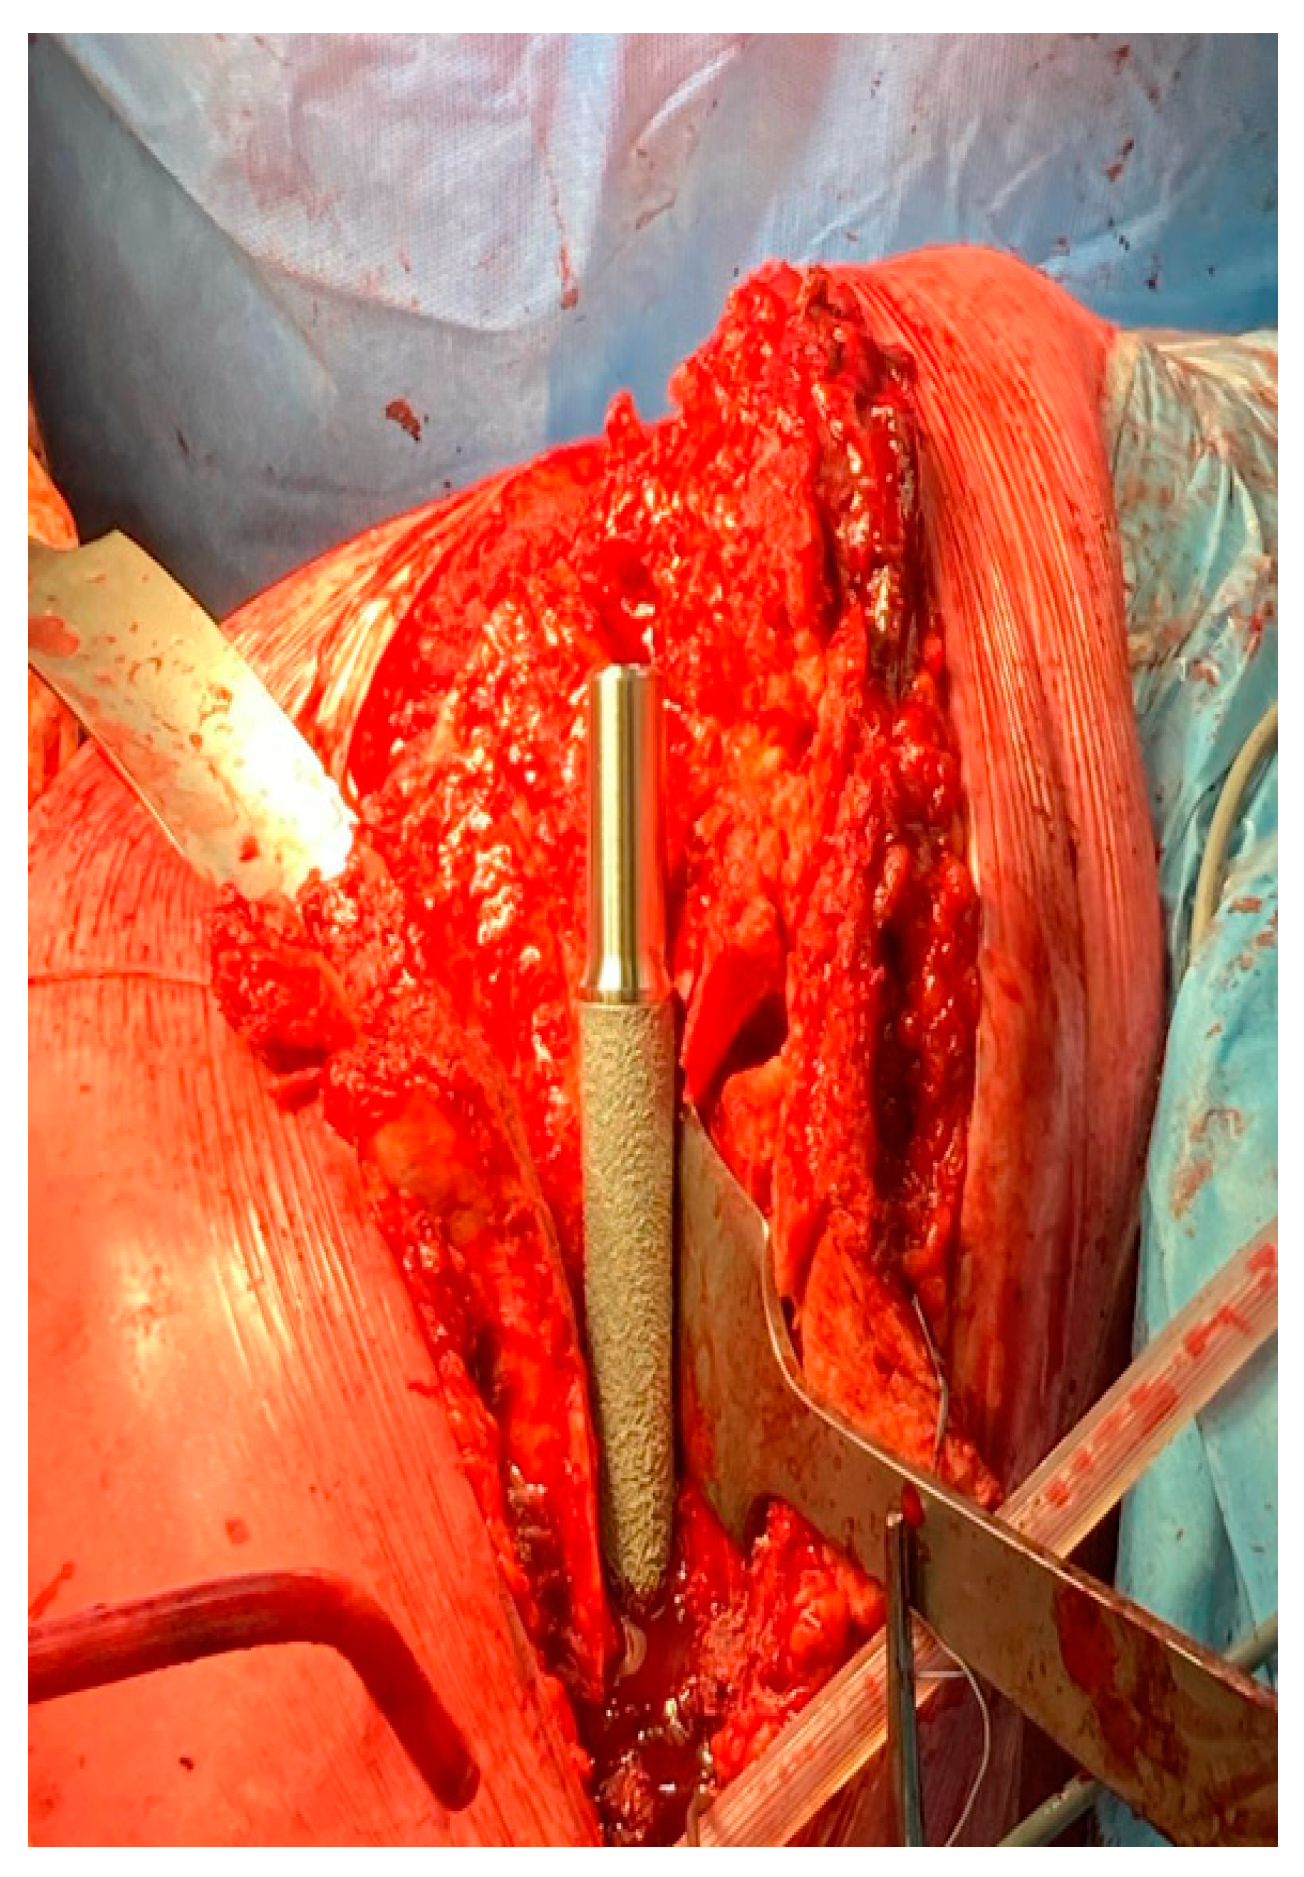

1.1. Surgical Technique